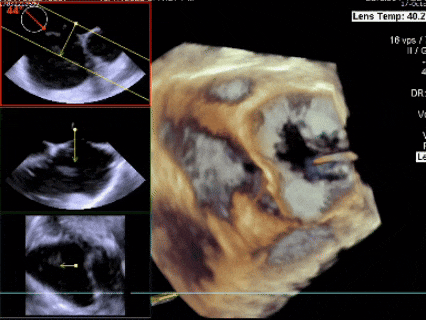

超声可见房间隔连续中断,彩色多普勒可见过隔血流

三维下可见房间隔缺损

三维下看到导丝成功过隔